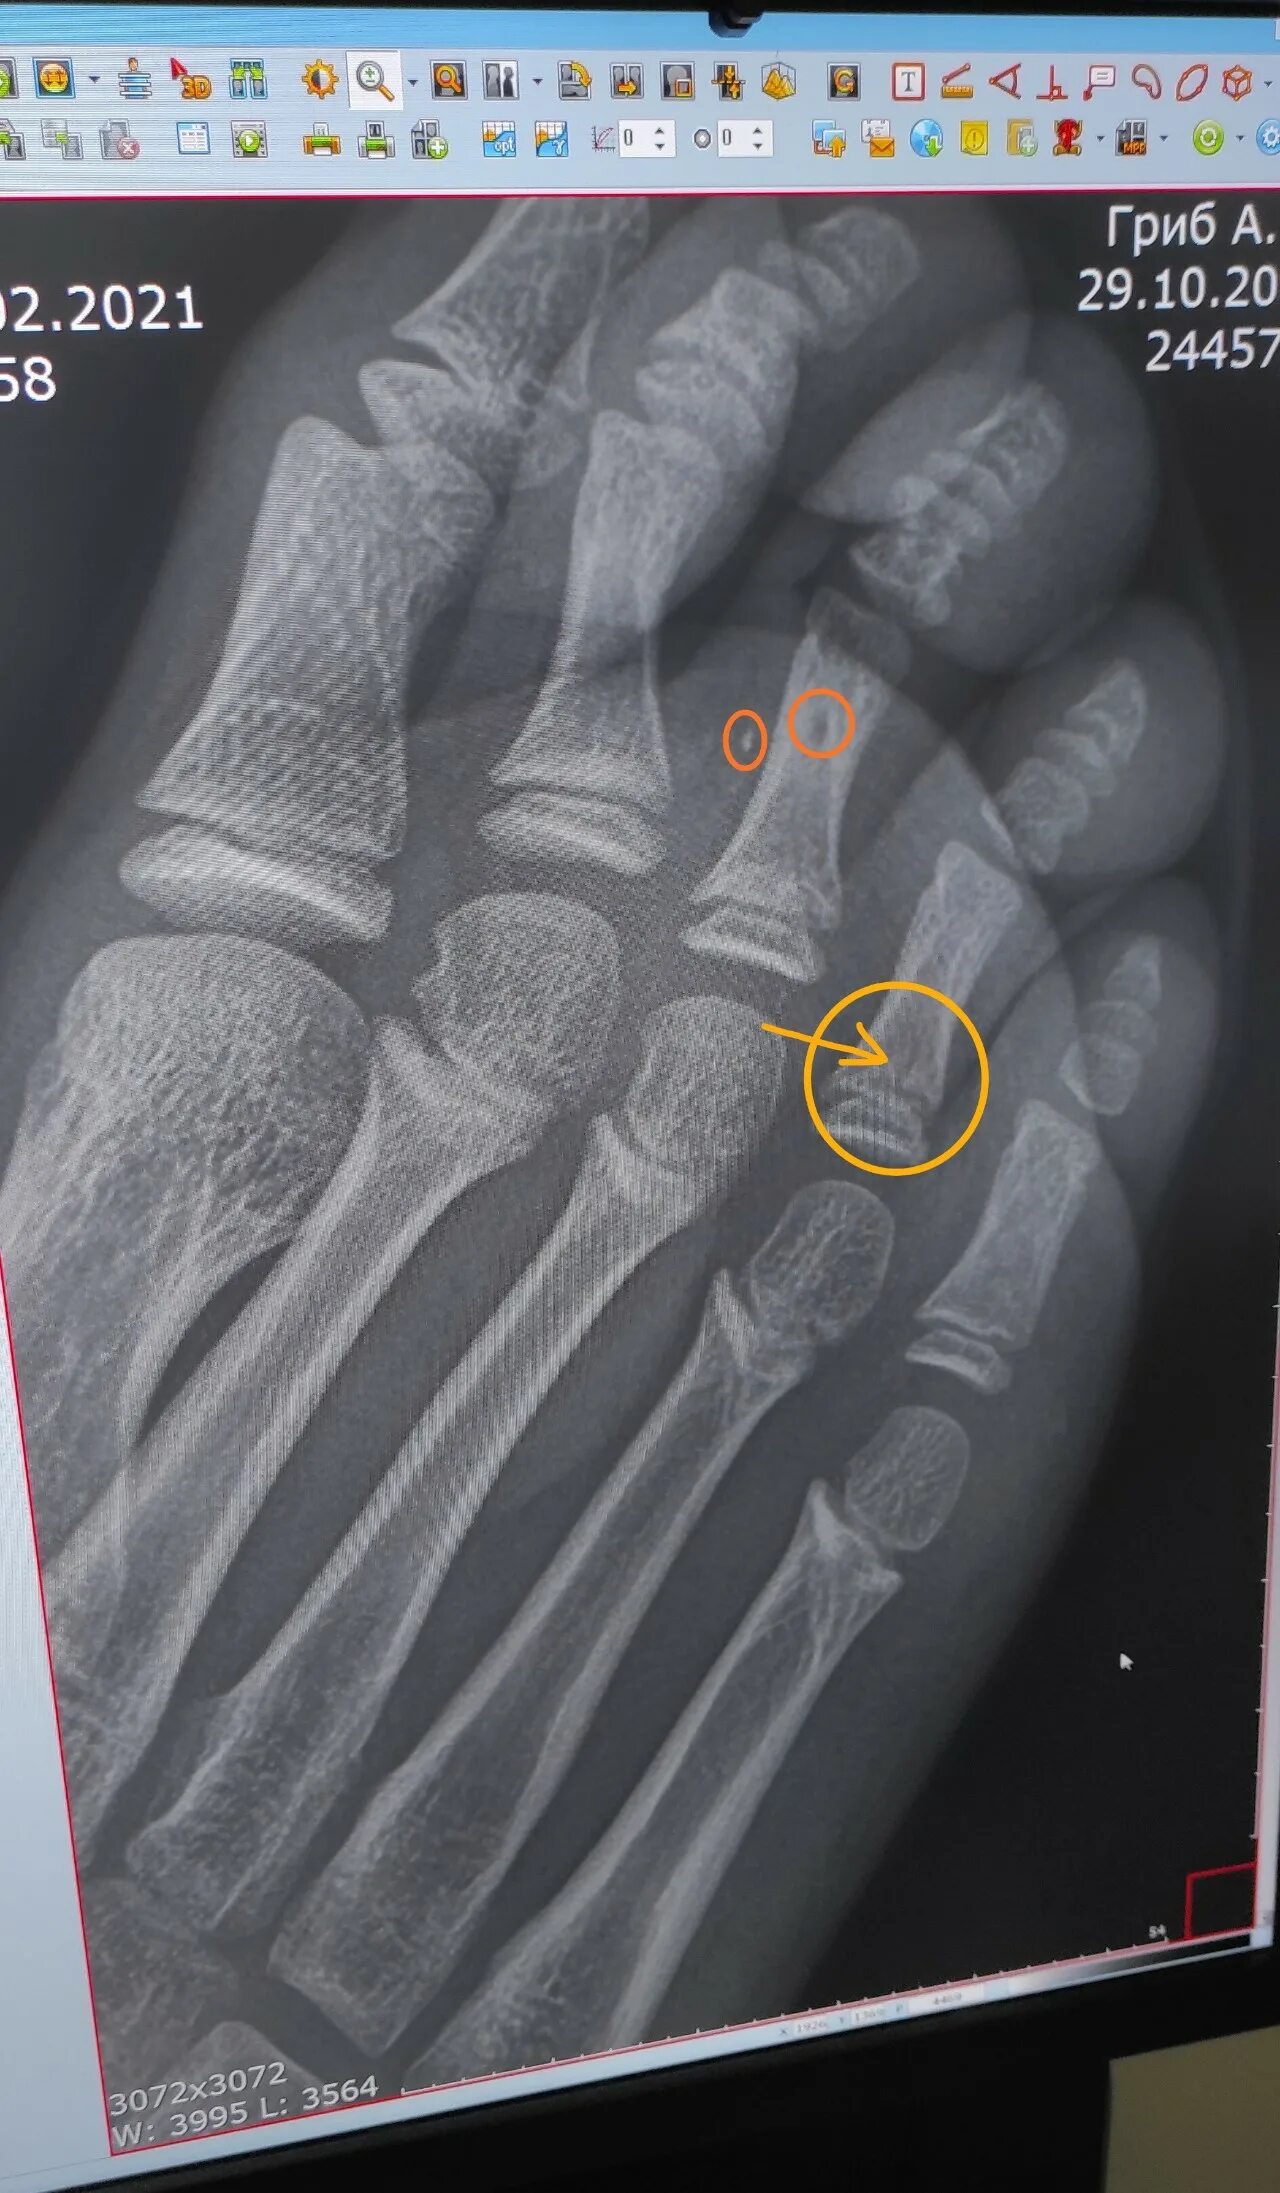

Закрытый перелом пальцев стопы мкб 10